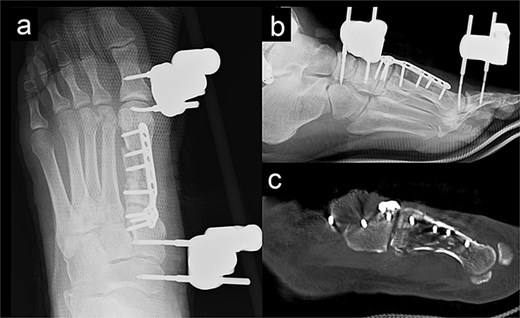

A 52-year-old man presented to our hospital with pain in the left ankle and forefoot after his left foot was caught in a wall while operating a tiller. Deformity was observed in the left ankle joint and the left forefoot. No evidence of neurovascular injuries or wounds was observed. The patient had a history of diabetes and hypertension. Radiography showed fractures of the left first metatarsal (Fig. 1a and b), tibial pylon, and distal fibula. Computed tomography (CT) revealed that the base of the first metatarsal was comminuted (Fig. 1c), and a dorsal skin prominence was identified due to a displaced dorsal fragment.

Radiography (a, b) and computed tomography (c) images of the left forefoot showing the comminuted first-metatarsal fracture.